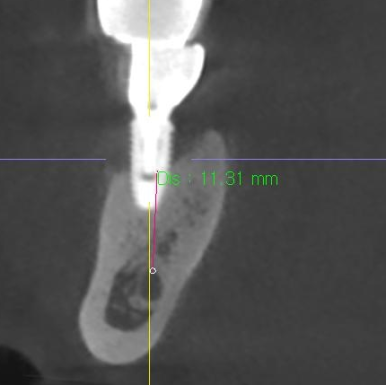

❗ 뼈까지 염증 진행된 경우 (주의)

✔ 픽스처 주변 골 손상

✔ 임플란트 주위염

→ 단순 AS 불가

→ 재치료 필요

👉 정확한 판단은

CT 촬영으로 확인합니다.